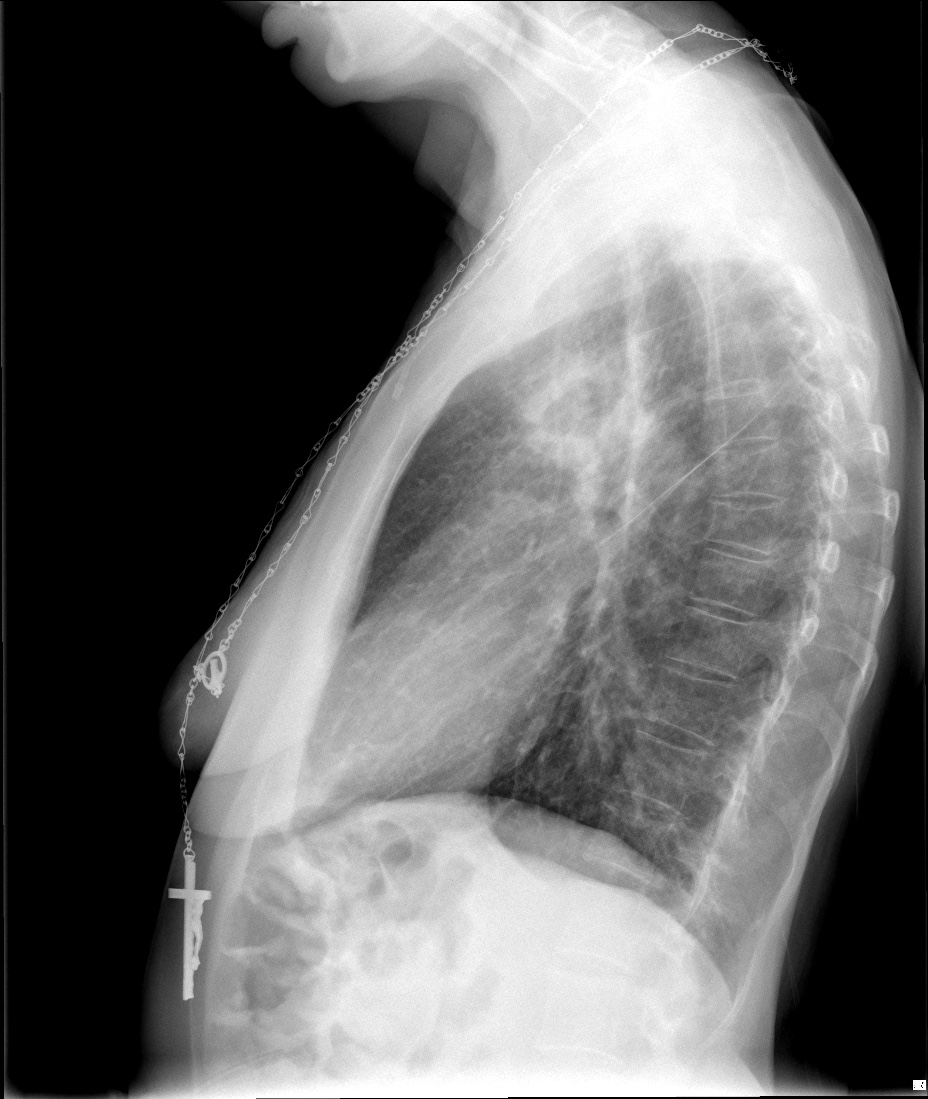

CASO: Febrícula y tos de 4 días de evolución.

Hallazgos:

- En la placa PA se observa una asimetría en los hilios pulmonares, el hilio izquierdo tiene una densidad aumentada.

- Tras examinar la placa lateral se observa un aumento de densidad en la columna que puede ser compatible con una condensación, es el signo de la desnificación vertebral.

SIGNO DE LA DENSIFICACIÓN VERTEBRAL: En la radiografía lateral normal, la densidad de la columna torácica tiende a disminuir desde la parte superior hasta el diafragma; la alteración de ese patrón por la presencia de una densidad superpuesta a la columna, indica la existencia de una consolidación pulmonar. Este signo adquiere especial valor cuando en la proyección posteroanterior la consolidación está oculta en el espacio retrocardíaco o en la base pulmonar.